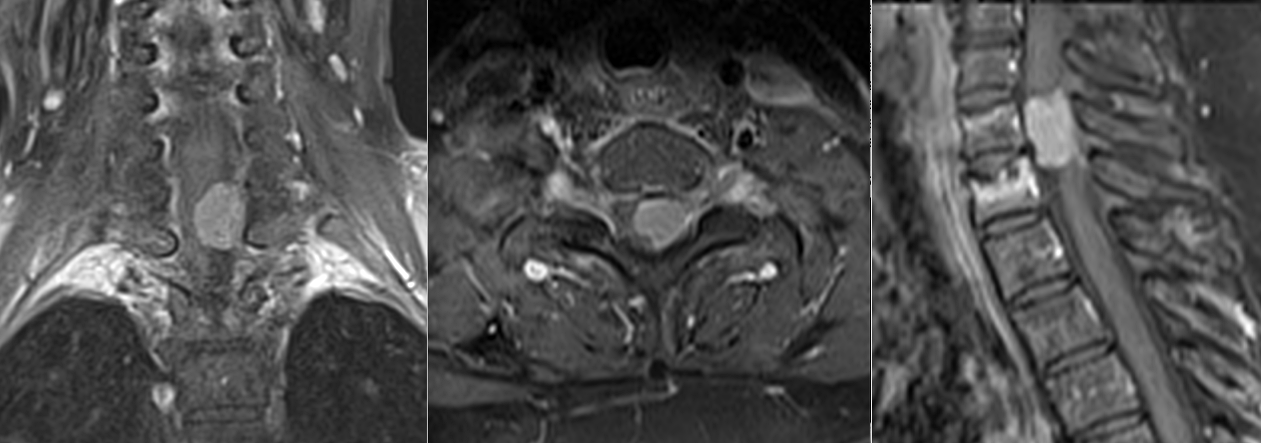

Abordul a fost posterior, cu laminectomie la nivelul C7–T1, adaptată expunerii optime a leziunii.

După deschiderea durei, tumora a fost identificată ca o formațiune bine delimitată, aderentă la dura mater pe partea stângă.

Disecția s-a realizat sub microscop operator, cu separarea progresivă a tumorii de măduva comprimată.

Pe măsură ce tumora a fost excizată, măduva și-a recăpătat treptat forma și poziția.

Semnalele de neuromonitorizare au rămas stabile pe tot parcursul intervenției, confirmând protejarea funcției neurologice.